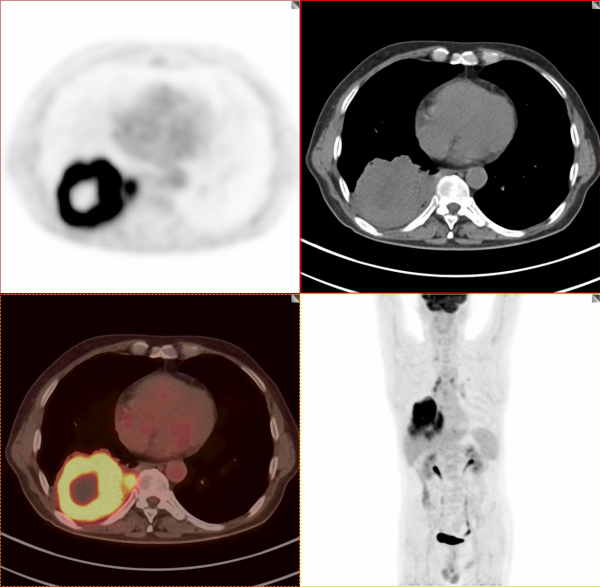

依據影像學分期,該患者後續進行了綜合治療:免疫+化療+靶向治療,其中化療3期,免疫治療2期及靶向治療。3個月後患者再次進行了PET/CT檢查,對治療效果進行了評估。2021年11月PET/CT檢查結果:

腫瘤病灶明顯縮小、實性成分明顯減少,腫瘤FDG代謝明顯減低,相鄰胸膜浸潤明顯改善,已經沒有胸水徵象。另外,全身其他部位未見明確轉移性病變。

複查後PET/CT診斷:右肺下肺癌綜合治療後,腫瘤病灶明顯縮小,FDG代謝明顯減低,相鄰胸膜未見高代謝病變,考慮腫瘤治療後療效顯著,僅少量腫瘤活性殘留。

根據我們PET/CT診斷,患者第二天就進行殘餘右肺癌病灶的手術切除。透過上述綜合治療,將一個原本沒有手術機會的患者從死神的手中搶回來。雖然愈後情況有待進一步觀察,但是透過PET/CT評價,患者病情明顯好轉,身體素質明顯好轉,生活質量明顯提高,將不可能變為可能。後續進一步療效,我會密切關注,後期隨訪再和大家分享。